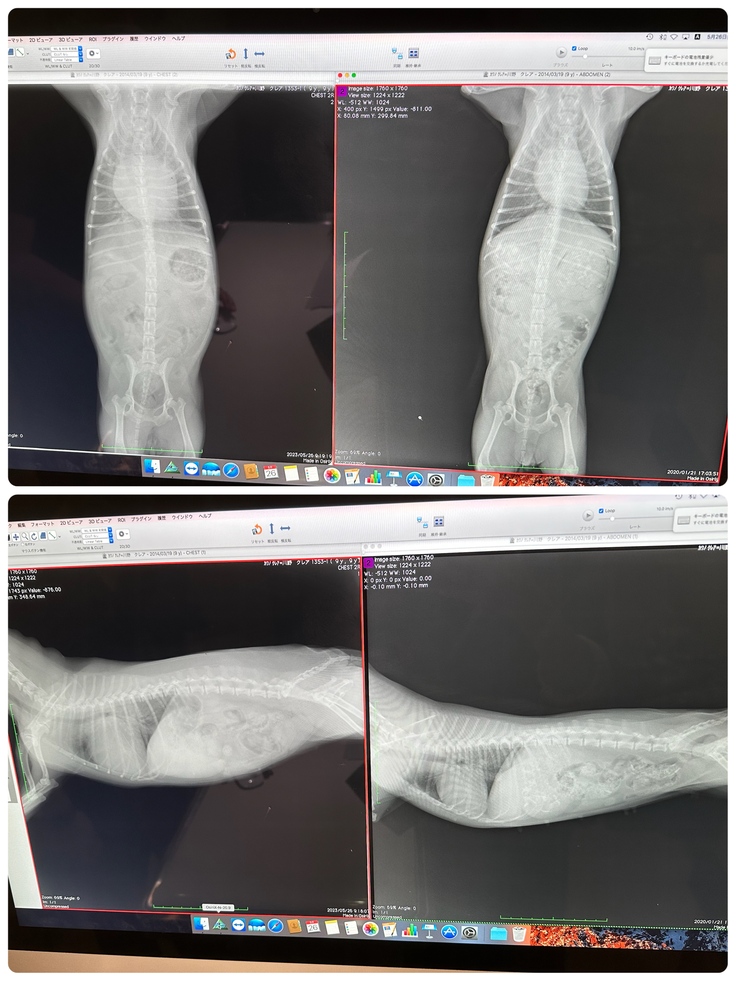

※右が3年前、左が病気が発覚した際のクレアの心臓です。

下記はその時説明を受けた写真です。

手術を予定している病院で再度詳しく検査をしてもらったところ、心臓はさらに大きくなっており、利尿剤を投与していなければ肺水腫になっていてもおかしくない状況からステージCと告げられました。

下記手術を予定している病院から作成いただいた診断書です。